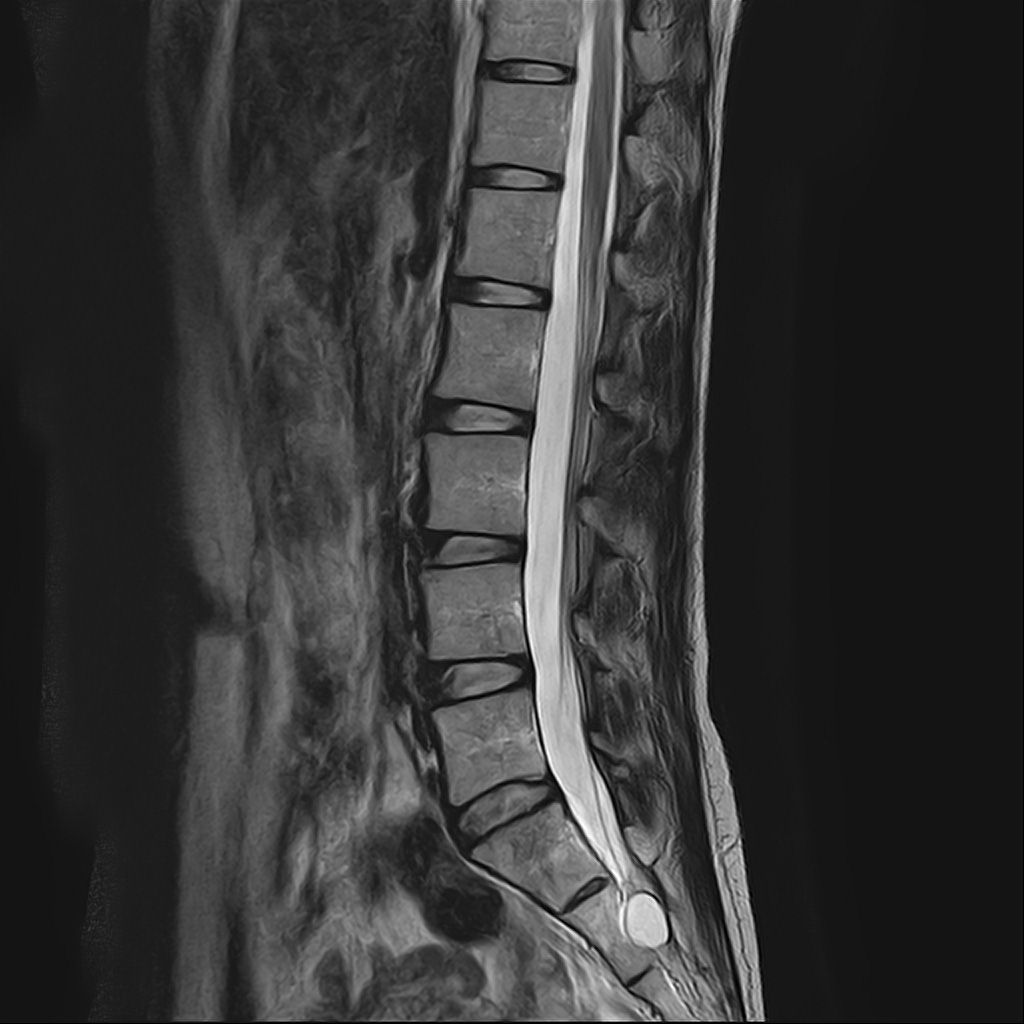

낭종s1-3번까지 꼬리뼈쪽으로 크게 나있다고했고, 단면상으로는 s2,3번이 촬영이 안되서 확인이안된다합니다. 허리디스크가 미약하게 4,5번에 있다고 했는데,

• 1번 째 사진